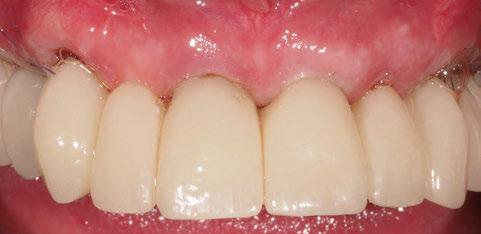

A las 24 horas se citó al paciente nuevamente, se atornilló el provisional en boca y se realizó una

Figura 24. Provisional finalizado tras acabado y pulido en el laboratorio.

Figura 25. Provisional finalizado tras acabado y pulido en el laboratorio.

Figura 26. Entrega del provisional de carga inmediata a las 24 horas.

Figura 27. Ortopantomografía del provisional atornillado en boca para verificar ajuste.

ortopantomografía de verificación del ajuste pasivo de todos los implantes. Por último, tapamos las chimeneas con teflón y resina provisional y se chequeó nuevamente la oclusión, dando nuevamente las instrucciones de higiene y mantenimiento de la prótesis provisional (Figuras 24-27).